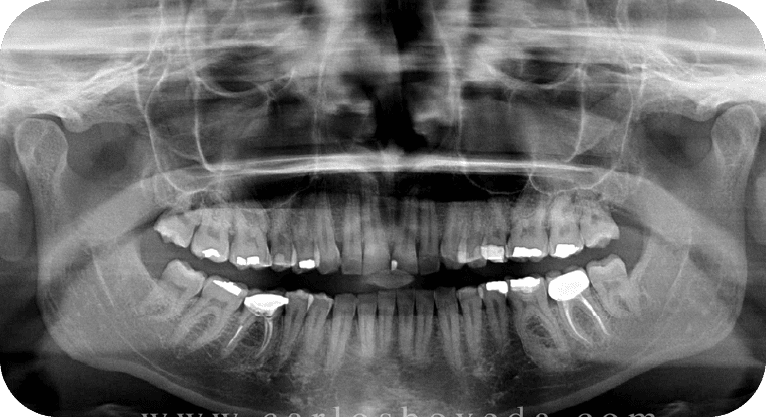

Paciente masculino, “32” años

Tratamiento: Tratamiento de conducto

El paciente requería tratamiento en dos dientes con pulpitis irreversible. Se realizaron endodoncias con microscopio y se restauraron las piezas según su daño, eliminando el dolor y evitando extracciones.